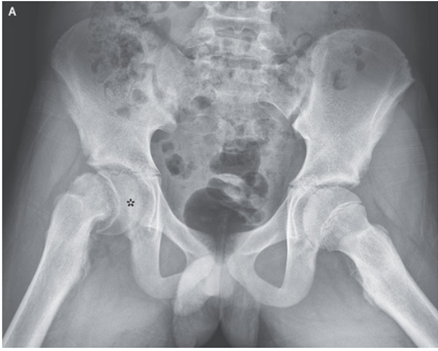

4歳男児。 2日前から右股関節痛と跛行を認め、整形外科受診。 これまでに外傷や発熱は特になかった。 診察上、どちら側でも股関節の可動域に制限はなかった。 やや右…